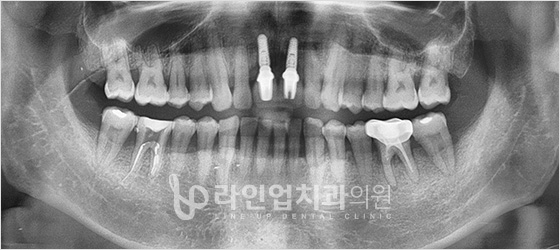

Before

After

Имплантация верхних моляров